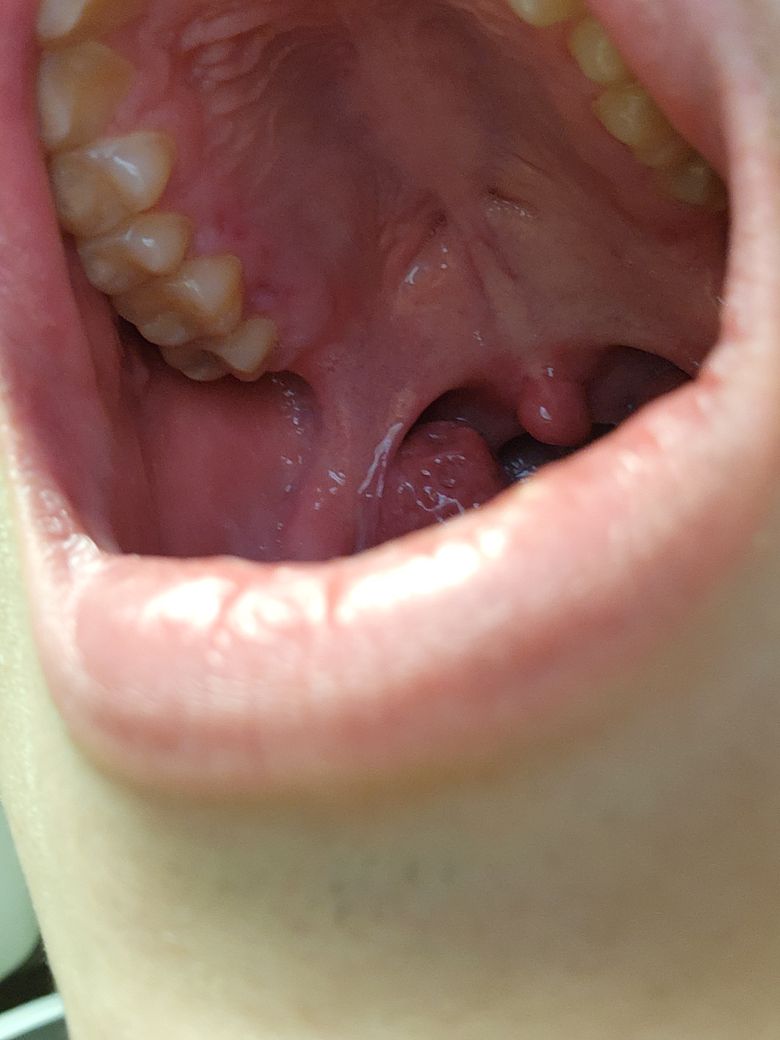

왼쪽 위 안쪽 잇몸의 붉은 점이 뭔가요?

일요일 부터 인가요? 갑자기 잇몸이 붓고 아프더라고요

그래서 보니까 잇몸에 빨간색 점이 있더라고요

안 건드리면 안 아픈데 음식이 닿거나 칫솔이 닿으면

통증이 있는데 이거 치과 가봐야 하나요?

사진만으로는 어두워서 정확한 원인을 알기 힘들어 보입니다.

사진상으로 보면 염증이 잇거나 그렇진 않지만, 뜨거운 음식을 드셔서 잇몸에 약간의 화상을 입으신거 같습니다. 시간이 지나면 괜찮아 지실꺼에요.